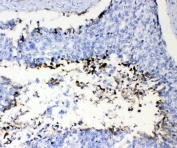

IHC testing of FFPE human colon cancer tissue with Prothrombin antibody at 1ug/ml. Required HIER: steam section in pH6 citrate buffer for 20 min and allow to cool prior to testing.

IHC testing of FFPE human lung cancer tissue with Prothrombin antibody at 1ug/ml. Required HIER: steam section in pH6 citrate buffer for 20 min and allow to cool prior to testing.